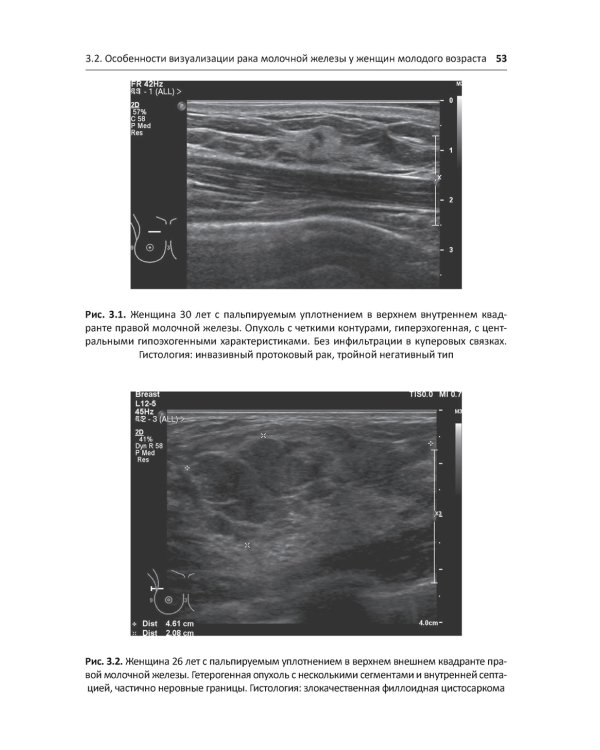

В книге представлены актульные сведения об эпидемиологии, факторах риска, биологических особенностях рака молочной железы (РМЖ), наиболее эффективные методы его диагностики. Определены показания к хирургическому, комбинированному и комплексному лечению с учетом прогностических факторов и степени распространенности опухолевого процесса. Обсуждены вопросы современной химио- и гормонотерапии в нео-адъювантном и адъювантном режимах лечения. Значительное внимание уделено методам лечения РМЖ у молодых женщин на последних стадиях болезни. Показана эффективность комбинированного и комплексного лечения РМЖ у молодых женщин и оценена возможность беременности после РМЖ. Издание предназначено широкому кругу специалистов - онкологам, хирургам, терапевтам, гинекологам, эндокринологам, а также ординаторам и студентам медицинских вузов.